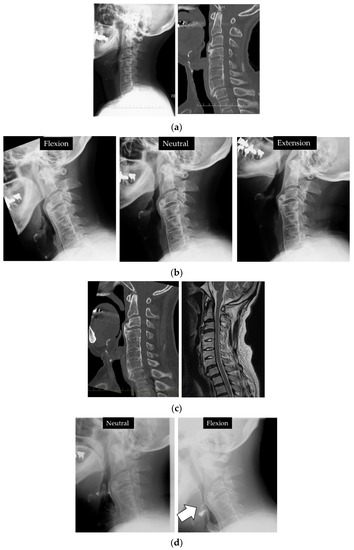

Ossification of the Anterior Longitudinal Ligament with Dysphagia as the First Symptom: Rehabilitation of Two Cases

2.5. Clinical Presentations